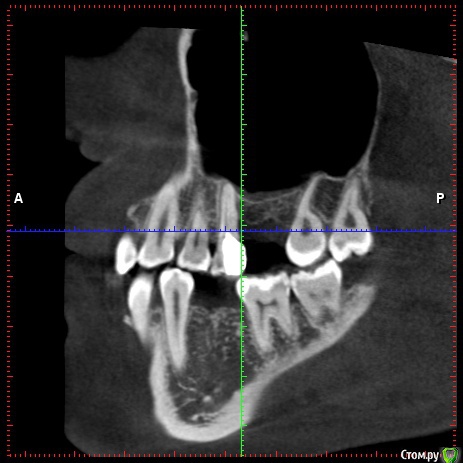

marilinka Опубликовано 28 февраля, 2016 Поделиться Опубликовано 28 февраля, 2016 Уважаемые доктора! Дело в том, что 1 марта у меня назначена имплантация нижних 5, которых никогда не было, первичная адентия. Верхняя 5 с одной стороны сильно опустилась, ортопед предложил, убрать ее под коронку, предварительно обточив, чтобы хватило места для коронки. И все бы ни чего,если бы буквально в течение недели ситуация во рту не поменялась бы, передние зубы стали упираться в друг друга, не сильно и не всегда, как зубки "поставишь", есть ощущение, что на снимках норм прикус, а сейчас занижен. Присутствуют болевые ощущения в скулах и висках, щеки пропали и самое страшное появилась носогубка. Доктор по поводу этого говорит, что протезируемся именно для этого, чтобы разгрузить сустав. В чем собственно мой вопрос хватит ли места для нижней пятерки, с той стороны где нет 2 зубов? Есть ли занижение прикуса и как с этим быть если есть? Не усугубит ли имплантация состояние внчс? Может стоит сделать новый снимок, слепки, которые кстати не делали и отложить пока имплантацию, раз у меня есть ощущение изменений во рту? С доктором общалась только по телефону, когда начало это беспокоить, раньше 1числа в больницу не попаду, нахожусь в 200 км от нее. Доктору доверяю, про таких как он говорят золотые руки, в паре с ним ортопед кмн. Что смогла то прикрепила. Ссылка на комментарий

marilinka Опубликовано 28 февраля, 2016 Автор Поделиться Опубликовано 28 февраля, 2016 (изменено) http://s017.radikal.ru/i416/1602/ea/fce843bb39a7t.jpghttp://s019.radikal.ru/i631/1602/80/8cf8f17bcc98t.jpghttp://s017.radikal.ru/i431/1602/78/b66e5d9610f7t.jpghttp://s019.radikal.ru/i616/1602/61/7ccb6dbbeb23t.jpg Изменено 28 февраля, 2016 пользователем marilinka Ссылка на комментарий

marilinka Опубликовано 28 февраля, 2016 Автор Поделиться Опубликовано 28 февраля, 2016 Ну вот как то вот так зубки во рту находятся. Ссылка на комментарий

Lolopop Опубликовано 28 февраля, 2016 Поделиться Опубликовано 28 февраля, 2016 добрый вечер, места для пятерки хватит, действительно-имеется небольшой наклон следующего зуба в сторону отсутсвующего, имплантация на состояние внчс не повлияет, делайте смело Ссылка на комментарий